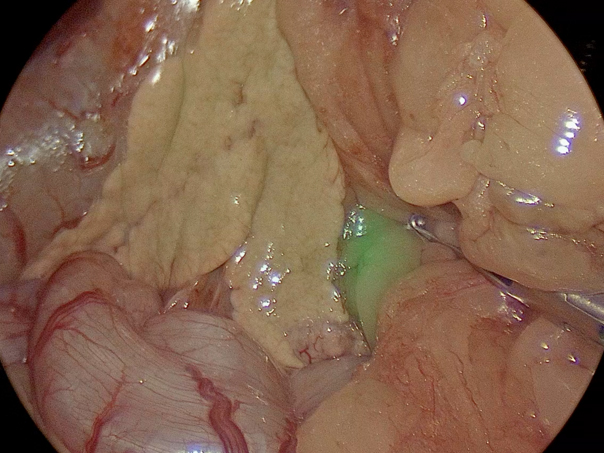

腹腔鏡カメラを用いて膵臓の確認、ICGを用いての膵臓腫瘤の辺縁の確認